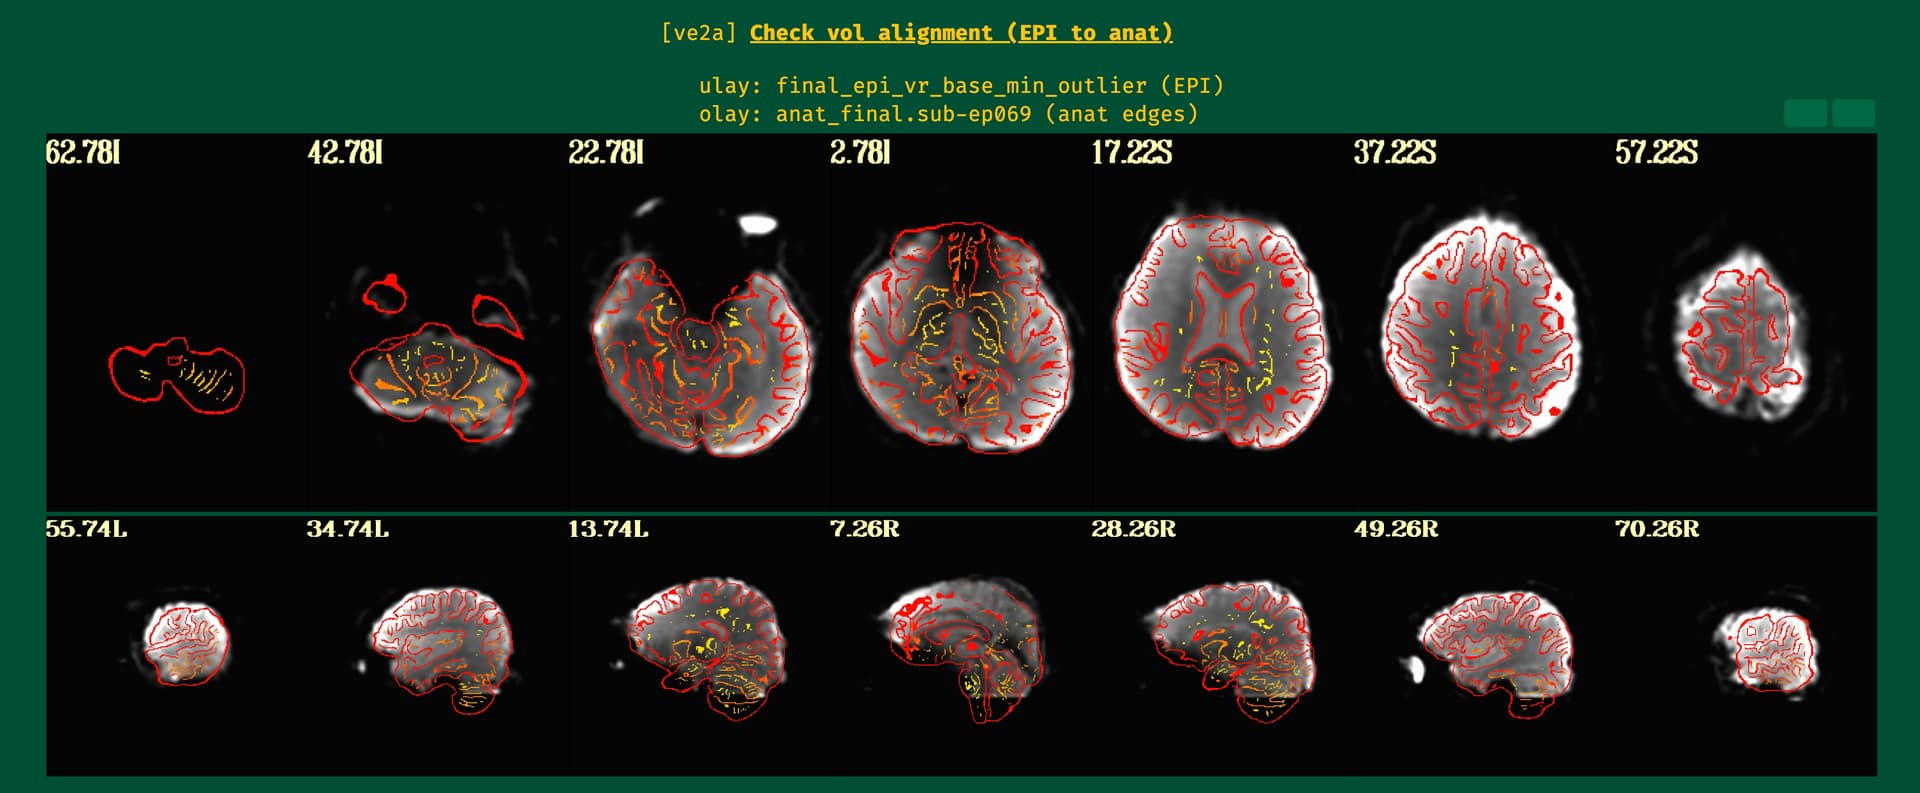

Then pb02_sub-ep069.r01.volreg is aligned with anatSS...

The epi to anat aligment looks fine in the QC